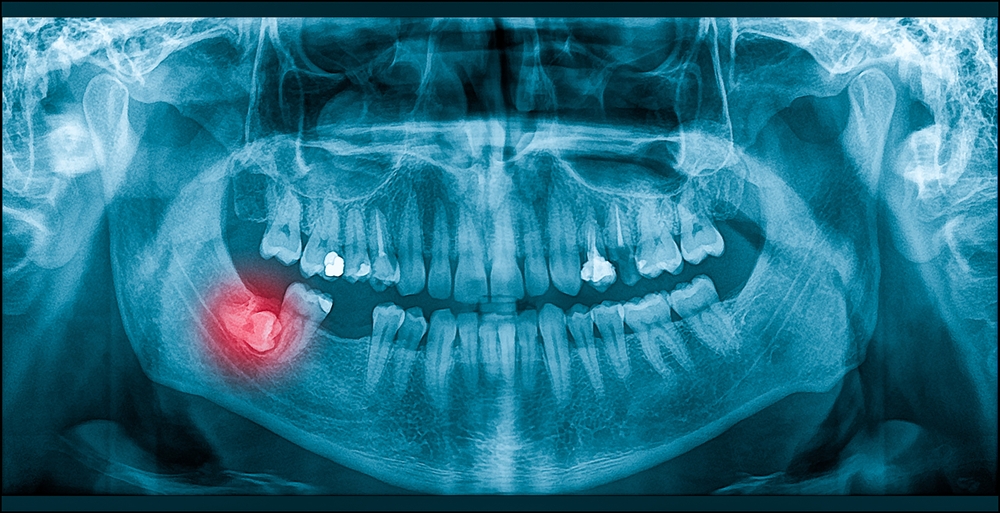

​Fjernelse af visdomstænder, rodspidsoperationer, operationer af cysterog isætning af implantater er blandt de indgreb, vi klarer her på tandlægeklinikken:

• En visdomstand, der ikke er vokset rigtig frem, skal eventuelt fjernes, så den ikke danner betændelse eller skader på nabotænderne.